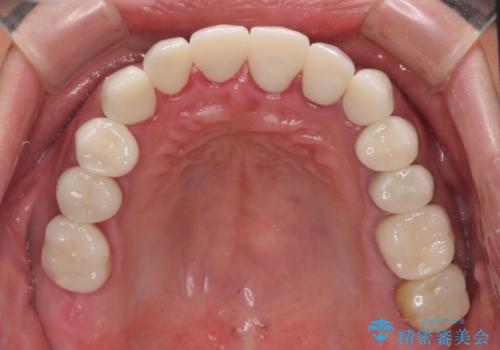

当初はむし歯処置が必要な歯のみの治療予定でしたが、捻転や咬み合わせを可及的に改善したいとのことで、全顎的にオールセラミッククラウンにて補綴治療を行うこととしました。

反対咬合を補綴治療で改善すると、上唇へ歯が当たる感覚や、発音時の舌感覚が急激に大きく変化するため、違和感になれるまで時間を要することになります。

仮歯で過ごす期間を一定期間も受けることで徐々に変化になれていくようにし、オールセラミッククラウン装着時には違和感なく過ごすことができるようにしています。